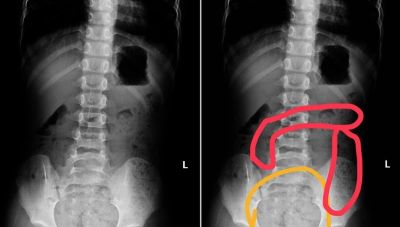

高雄一名11歲小學男童因腹痛、冒冷汗、嘴唇發紫及手腳冰冷被送至急診,經問診與腹部X光檢查後診斷為嚴重便祕。醫師替他灌腸後大量排便,症狀立即緩解。母親表示,孩子習慣邊上廁所邊玩手機,每次都拖太久被罵後匆忙結束,常搞不清楚是否有排乾淨。

另一名6歲女童因腹脹劇痛直哭,腹部明顯隆起,X光檢查顯示「腸道塞滿糞便」。母親推測,女兒剛上小學尚未適應課程節奏,有便意也常忍著不上廁所,導致多日未排便。